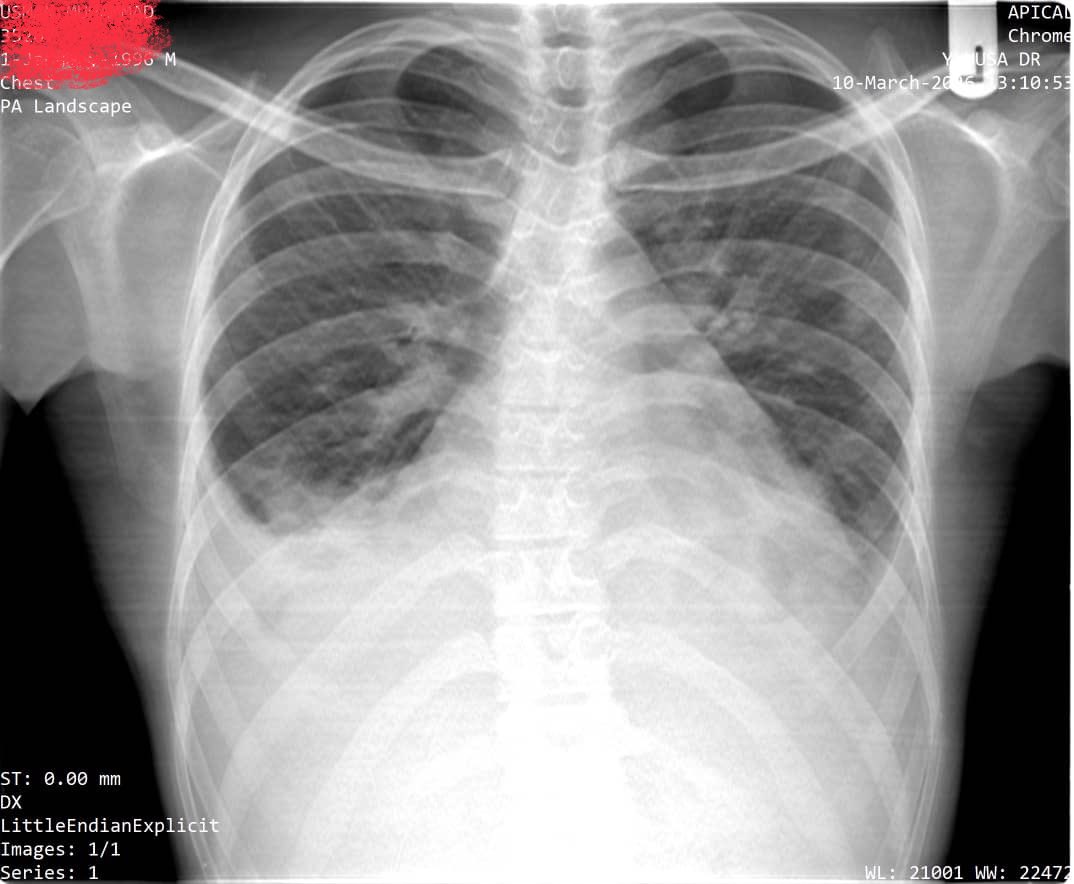

30yrs old Man with chest pain and difficulty in breathing! What do you think is going on? A. Chest infection B. Pleural effusion C. Pneumonia D. Cardiac failure #clinicalmedicine #clinical #Radiology

DrAyubaD's tweet image. 30yrs old Man with chest pain and difficulty in breathing!

What do you think is going on?

A. Chest infection

B. Pleural effusion

C. Pneumonia

D. Cardiac failure